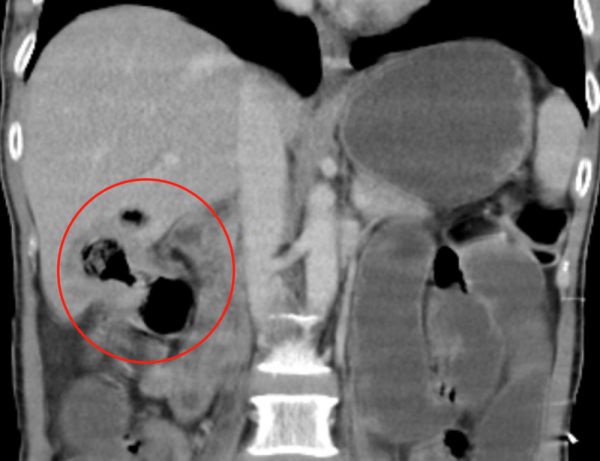

我父亲肠道的原发肿瘤,直接侵犯到了肝脏,物理上跨越了两个器官,也就是肿瘤一半在肠子里,一半在肝里。

受化疗的影响,原本实心的肿瘤,在药物的作用下内部坏死,变成了空心的,因此形成了CT报告上所描述的——“与肠腔相通,结肠-肝脏交通”的情况。

于是,肠子里的细菌、粪便便通过这个空腔,进入到了肝脏(图示中绿色箭头),与坏死的肿瘤组织混合成为肝脓肿。

而又因为肝脏血管丰富,细菌进而进入到全身血液循环中,导致了全身的严重感染。不幸中的万幸是,因为肝组织和肿瘤自身将脓液给包裹住了,所以这些细菌几乎没有流进腹腔(如下图CT红圈所示)。